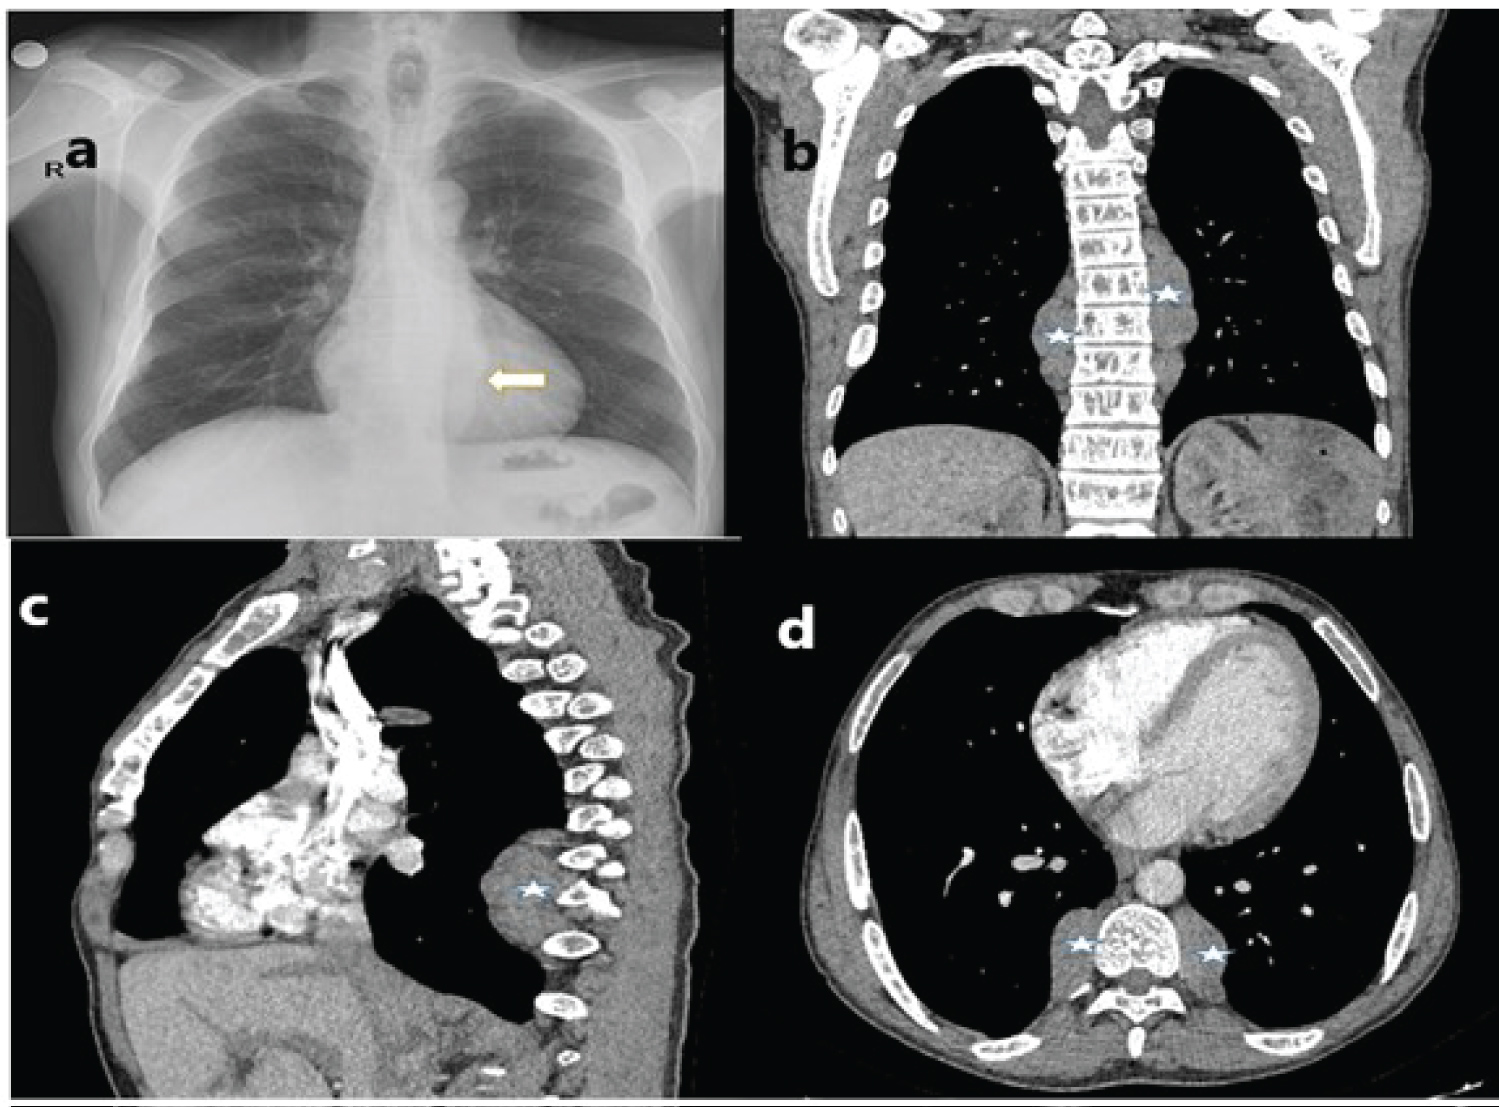

A 52-year-old male patient was referred to our outpatient clinic with complaints of cough, hemoptysis (minimal), and chest pain radiating to the back. The patient's smoking history was five packs/year, and he was yet an active smoker. On physical examination, respiratory sounds and other system examinations were normal. In laboratory tests, the hemoglobin level was 6.7 g/dL, platelet was 986000 u/L, leukocyte was 13500 u/L, ferritin was > 2000 ng/ml, sedimentation was 2 mm/h, and C-reactive protein was 0.1 mg/L, and renal and liver function tests were normal. The patient, who underwent intermittent erythrocyte transfusion for 15 years with the diagnosis of thalassemia intermedia, was splenectomized. A paraspinal mass was observed in the chest X-ray and then on the thorax computed tomography (CT) (Figure 1).

Figure 1: Radiological imaging findings (a) Increased paravertebral density marked by an arrow on chest X-ray; (b) A paraspinal mass marked by an asterisk is observed in the coronal section of the thorax CT; (c) In sagittal section; (d) In the axial section.